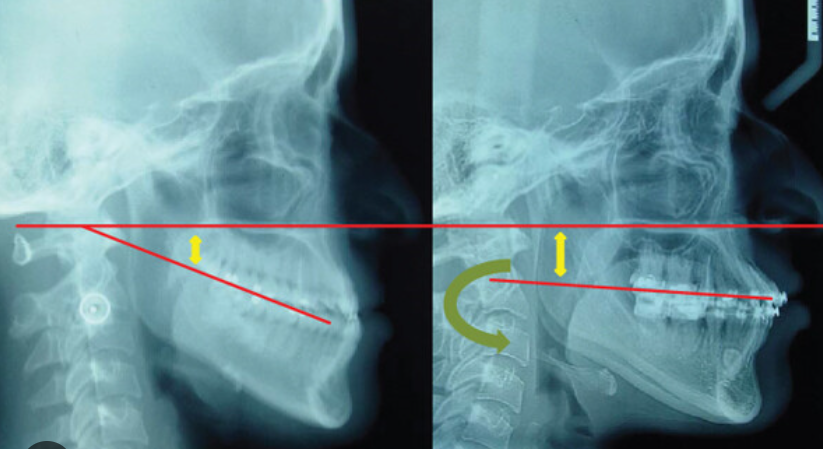

For better or worse, I received camouflage orthodontics, beginning with a first set of braces / Herbst Appliance / palate expander around the age of 10-11 that lasted around 1-2 years, and a second set of braces around the age of 14 that lasted around 3 years, till I turned 17. Modern camouflage orthodontics are so good that the appearance of the face from a head-on view appears almost entirely normal (Ex. Michael B. Jordan). However, the side profile is still obviously recessed. A downside of camouflage orthodontics is that counter-clockwise rotation can no longer take place during double jaw surgery -- camouflage orthodontics artificially straighten an angled malocclusional plane. An example of this is show below.

Image 6a/b (red lines): Adenoid face with modern camouflage orthodontics. Face appears almost "normal" from the front yet still shows recession from the side, albeit relatively less so than what would have been without orthodontic treatment. Frontal chin-mouth ratio appears normal. Airways remain impacted.

Camouflage orthodontics can possibly be considered as a "crime to the uninformed."